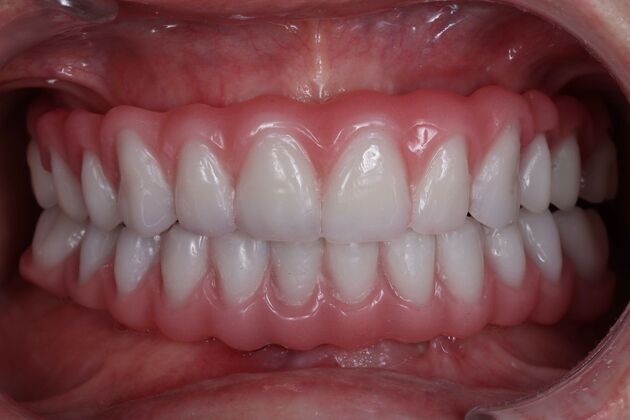

Dental Implants: Silvia - Fixed Hybrid denture

Description

In Silvia's case, the use of a removable denture that didn't fit well leave her with low self-esteem and not wanting to smile. In her case, after analyzing her profile, we have created a total fixed prosthesis to achieve a natural and harmonious smile. Today dentistry often restores not only oral health, but the general health of the patient.